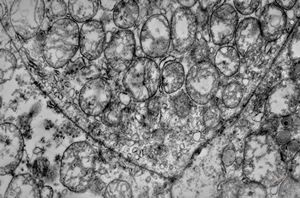

M,41y. | ribosome-lamella complex in tricholeukocyte -hairy cell leukemia, spleen